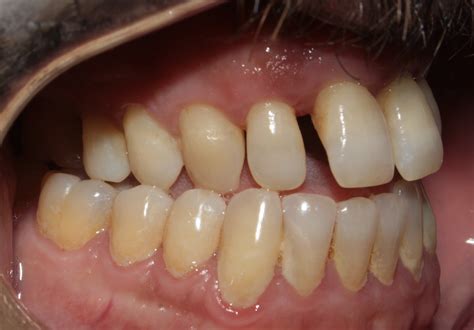

Orthodontic Correction of Midline Diastema in Aggressive Periodontitis

Orthodontic Correction of Midline Diastema in Aggressive Periodontitis ...